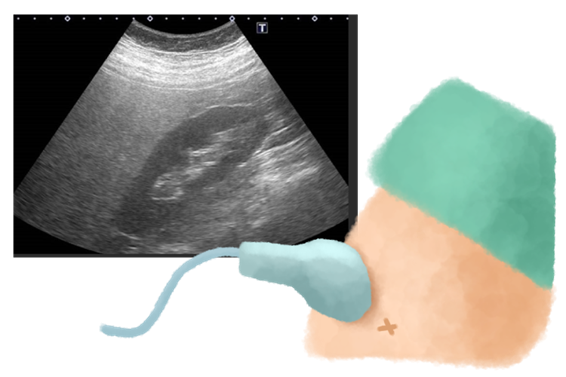

当院では、腹部エコー(超音波)検査を推奨しています。

- 正確性: 医師が直接、超音波を使って内臓周りの脂肪の厚みや量を「見える化」し、客観的に評価できます。ご自身の目で脂肪のつき具合を確認することで、治療への意識も高まります。

- 安全性: CT検査とは異なり、放射線被ばくの心配が全くありません。体に負担をかけずに、繰り返し安全に検査を行うことができます。

- 付加価値: 内臓脂肪の蓄積と密接に関係する「脂肪肝」の程度を詳細に評価できます。脂肪肝は、放置すると肝硬変や肝がんへと進行する可能性があるため、その早期発見は非常に重要です。